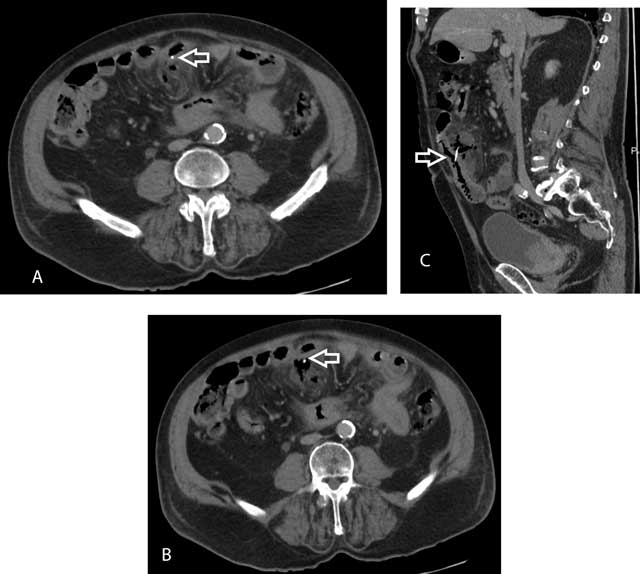

Figure 1

Axial (A and B) and sagittal (C) reformations shows linear high-density structure (arrow) within the inflammatory mass and in continuity with the adjacent small bowel lumen.